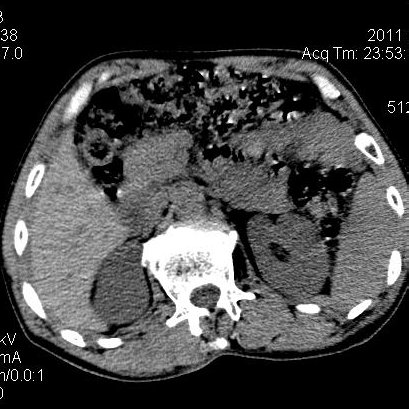

肝左叶发育异常

男性,55岁,骑摩托车摔倒后入院,自述右上腹疼痛

[backcolor=#FF0000]第一次诊断的时候也是这么肯定,可是床旁超声检查并没有发现明显异常,而且患者的一般症状都良好。还好临床只是保守治疗,没有立即手术,第二次复查的时候没有一点变化,又做了MRI检查,没有血肿,

这是一例肝左叶发育异常的,很个性吧~[/backcolor]